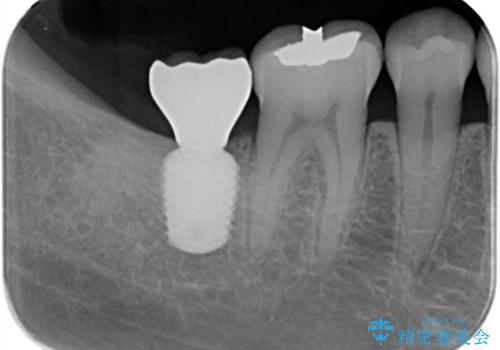

- 奥歯が痛いことを主訴に来院されました。

重度の歯周病により保存困難と診断し、抜歯後にインプラント治療を行いました。

抜歯後十分な骨の回復が認められず、単独の骨増生を行った後にインプラントを埋入しました。